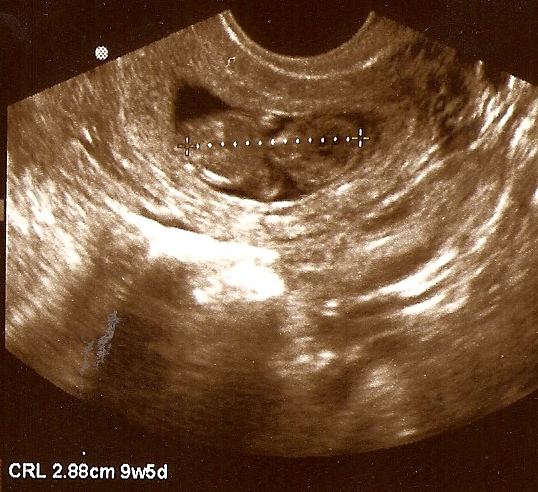

In April, we announced to our family and friends, and then everyone else, that we are happily expecting Baby Number Two. May 1st was our first prenatal appointment and our first view of this little one. According to her size during that ultrasound, she is due on November 30th, although Dan and I suspect her actual due date may be a little earlier in November. I guess we’ll just have to wait and see. Here she is measuring less than 3 cm (just over an inch) at 9 ½ weeks gestation: